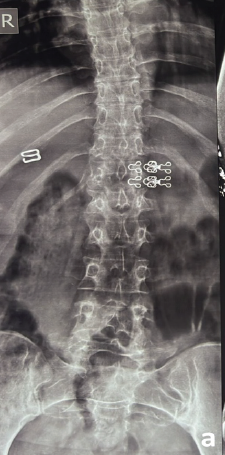

Pregnancy and Lactation Associated Osteoporosis in a 24-Year-Old Presenting with Multiple Fragility Fractures in the Dorsolumbar Spine: A Case Report and Review of Literature

Tejas Gandhi , Pramod Bhilare , Parag Sancheti